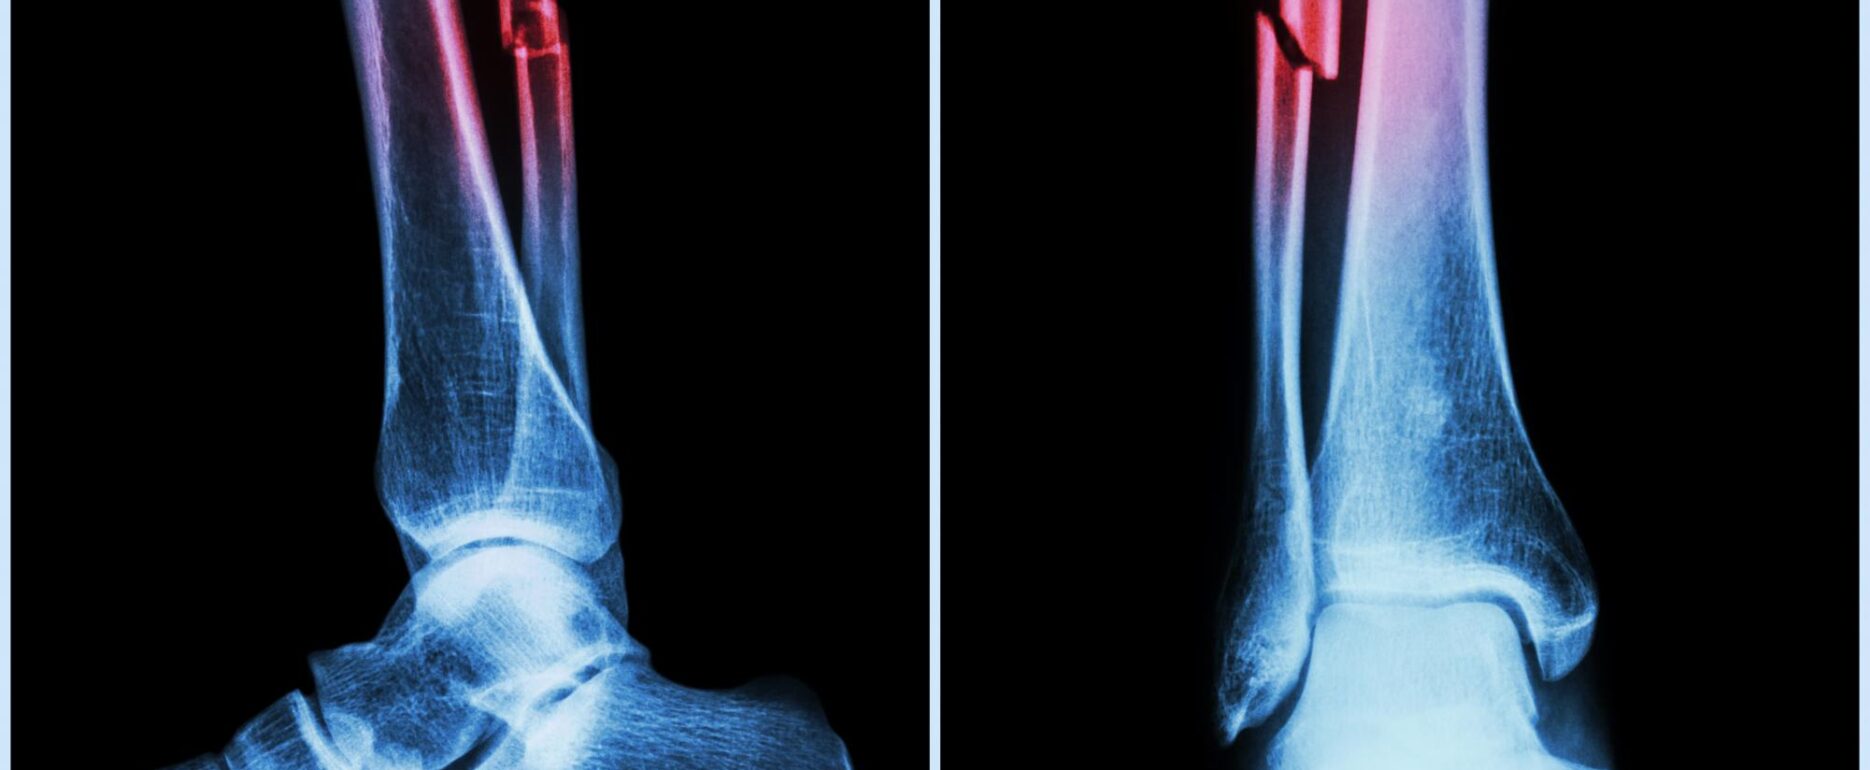

A-hus tar i bruk beinbrudd-KI

KI-algoritmen skal først implementeres i klinisk drift på Ski sykehus 1. oktober 2024.

Vestre Viken var først i Norge med å teste løsningen på røntgenbilder ved mistanke om brudd, høsten 2023. Siden oppstart har over 15 000 pasienter blitt diagnostisert ved støtte fra KI og over 4100 pasienter har sluppet ventetid ved legevakt, akuttmottak og røntgenavdeling.